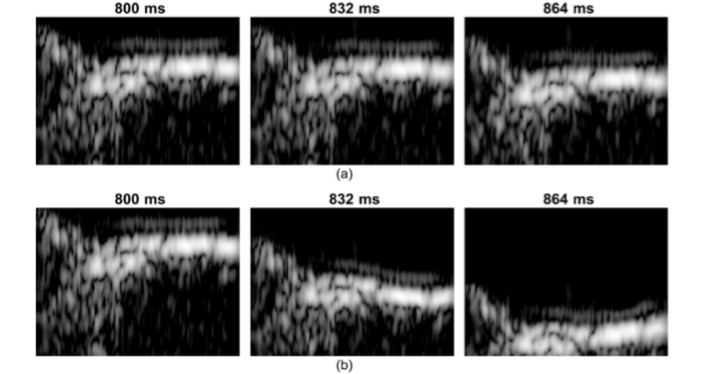

Figure Legend: Demonstration of video magnification applied to medical ultrasound imaging for one example with ultrasound (carotid). Close-up views of the distal wall are presented over time at 800, 832 and 864 ms after the beginning of acquisition. Upper row (a) is the original US images and the lower row (b) is the magnified data. Radial motion, due to the propagation of a pulse wave, is only visible on the magnified data (b).

"Video Magnification Applied in Ultrasound" IEEE Transactions on Biomedical Engineering. Vincent Perrot, Sébastien Salles, Didier Vray and Hervé Liebgott. IF = 3.577